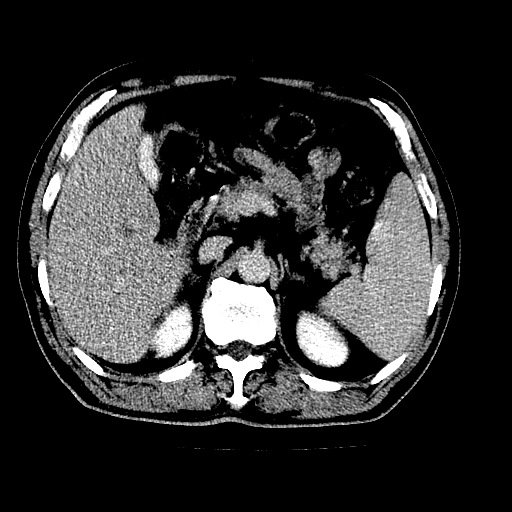

男,66岁,上腹部不适、黄染一周。彩超示:肝左叶占位,肝内胆管扩张,胆总管扩张,胆总管占位?

肝左叶占位性病变,并胆管扩张,符合胆管细胞癌ct表现,门脉左支受累,左肾囊肿。窗宽太窄了,其他的看不清

左叶胆管细胞癌累及胆总管,门脉左支受侵,慢性胆囊炎胆结石,左肾小囊肿

肝左叶不规则软组织肿块影,边缘不规整邻近肝实质受累分界不清;肝内胆管(左叶)明显扩张成“软藤状”,诊断:肝左叶胆管细胞癌。胆囊钙乳症。